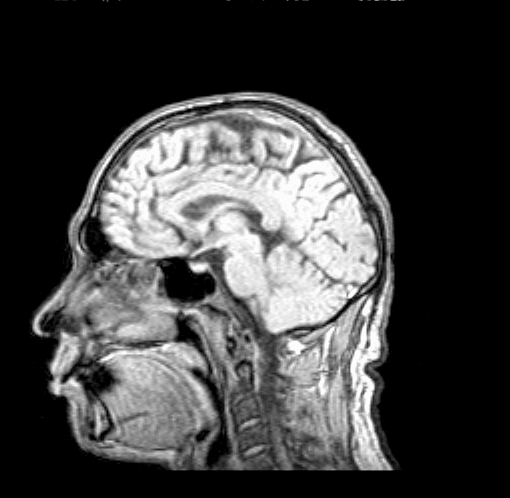

Требования к передаче телемединформацииДля решения большинства задач телемедицины необходим режим телеконференции, когда врачи в отдаленном медицинском учреждении и в центральном институте видят друг друга и пациента, могут разговаривать между собой. Однако этого недостаточно, поскольку основную информацию при сложных диагностических случаях врач получает в виде изображений внутренних органов или биопсий. Это — микроскопические, рентгеновские, ультразвуковые, радиоизотопные исследования и их более сложные и аналоги, как компьютерная томография, динамическая ангиография. Поэтому системы телемедицины (СТМ) должны быть готовы к передаче (без потери качества) следующих видов информации: изображения, получаемые с диагностической аппаратуры, аналоговые сигналы, таблицы закодированной информации и/или свободный текст.[16] Необходимы единые стандарты для объединения разнородных форматов изображений и создания единого цифрового набора для его дальнейшей пересылки. Существующие в Германии "Sienet", в США "PAКS" и другие еще не удовлетворительны по "интеллектуальной" наполненности , поэтому аналогичные подходы развиваются в России (в МГУ, ИКИ и др.) на уровне, заметно превосходящем упомянутые коммерческие системы. Требования к аппаратуре для передачи и воспроизведения изображений высоки. При воспроизведении компьютерно—томографических, рентгеновских и ультразвуковых изображений необходимы не менее 256 градаций "серого" цвета. Высокой должна быть и скорость передачи изображений. Поэтому во избежание быстрого морального старения системы необходимо закладывать скорость передачи порядка 2,048 мБит/с. Существенную часть информации о больном составляют аналоговые сигналы (ЭКГ, ЭЭГ, реограммы и др.), которые практически повсеместно эти кривые оцифровываются до введения в компьютер. Частотный диапазон всех физиологических сигналов не превышает 1 кГц, обычно у одного пациента регистрируется несколько (от 2 до 5) аналоговых кривых. Здесь будет требоваться разработка протоколов обмена информацией и стандартов на форматы передачи данных. Таблицы закодированной информации не будут составлять большого объема и не потребуют скоростей выше, чем при передачи изображений. Основные трудозатраты потребуются на формализацию медицинских данных и унификацию протоколов обмена информацией. Иначе будут неизбежными разночтения (а в результате — повторение диагностики) при переходе пациента из одного лечебного учреждения в другое. Передача свободных текстов не предъявляет особых требований к системе передачи информации, но избежать передачи свободных текстов не удастся, т.к. не вся медицинская информация может быть формализована и закодирована.[15] Для эффективной диагностики заболеваний (особенно хирургических) на одного пациента требуется получение от 3 до 20 изображений разного характера. Так, например, для диагностики опухолей печени и поджелудочной железы требуются компьютерно—томографическое, ультразвуковое, ангиографическое исследования одновременно. Для диагностики сердечных и сосудистых заболеваний необходимы рентгеновские, магниторезонансные, ангиографические исследования. Анализ возможности передачи медицинских данных существующими программно – аппаратными средствамиПри организации передачи данных от медицинского диагностического оборудования возникает ряд технических проблем, связанных с высокими требованиями предъявляемыми к качеству передаваемой информации. Эти проблемы можно разделить на три основные группы: